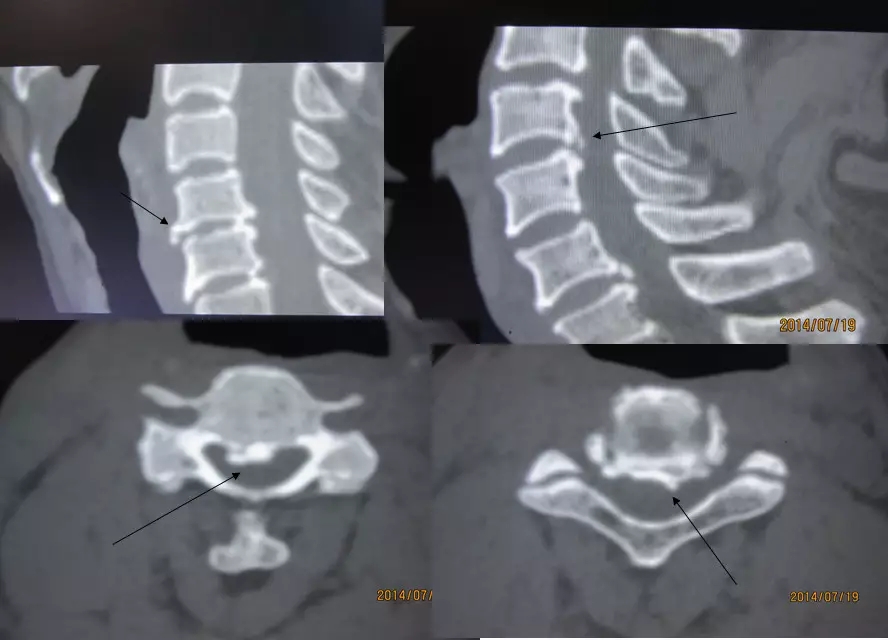

4.滑脱、峡部裂

腰椎前滑脱I度

椎弓峡部裂